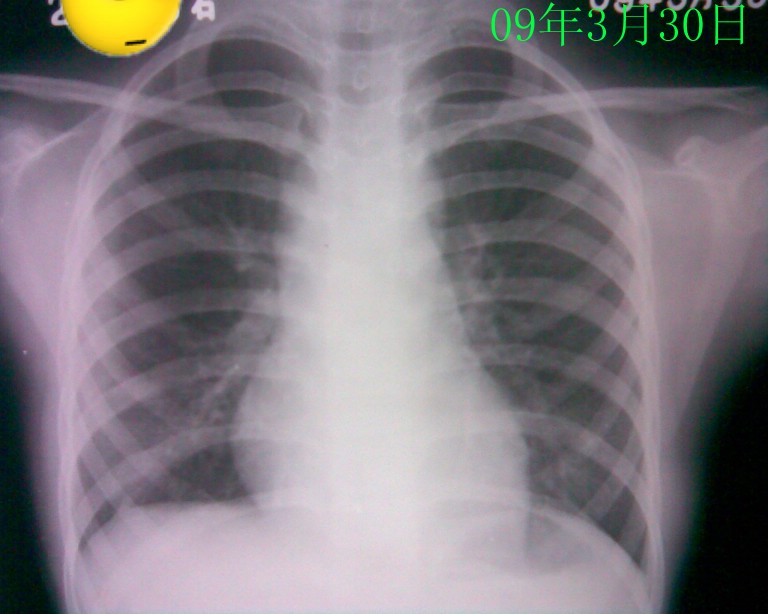

标题: PED1836:女,9岁,发热5天,听诊两肺呼吸音粗 [打印本页]

标题: PED1836:女,9岁,发热5天,听诊两肺呼吸音粗

节段性肺炎。典型!

节段性肺炎。典型!!!

节段性肺炎。片资料完整。